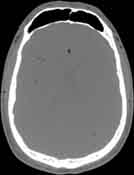

Visible Human male: Sectio transversalis 1073

CT

NMR

Pd T1 T2